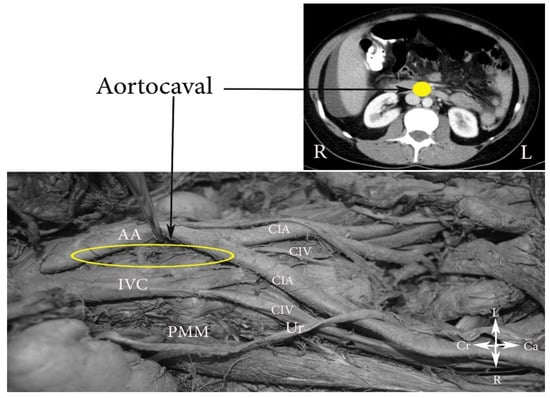

- The aortocaval or interaortocaval region (includes preaortic and precaval PALNs) is limited: ventrally—LRV, laterally—left—lateral aspect of the AA, right—lateral aspect of inferior vena cave, dorsally—AA bifurcation, caudally—prevertebral fascia, anterior longitudinal ligament and psoas major muscle.